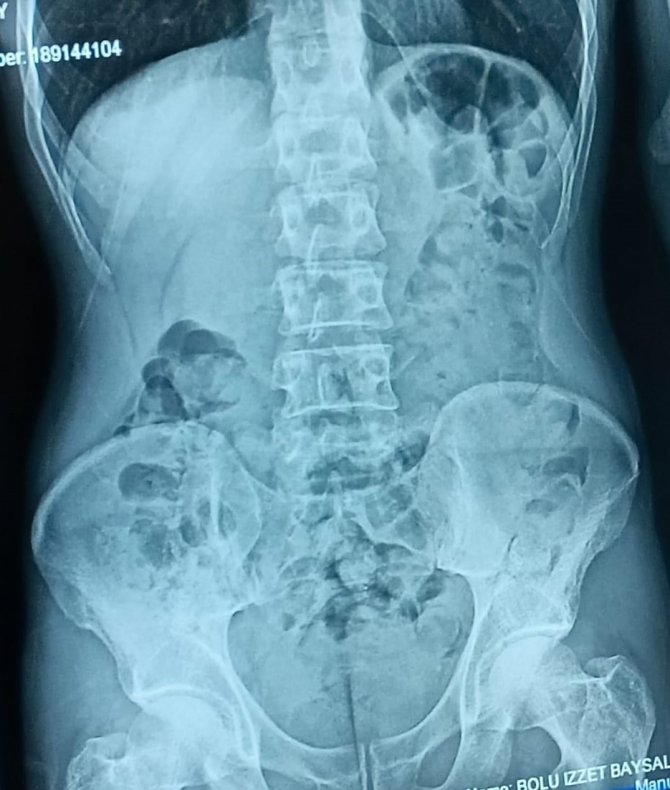

Edinilen bilgiye göre, İl Emniyet Müdürlüğü Narkotik Suçlarla Mücadele Şube Müdürlüğü ekipleri, doğu illerinden İstanbul'a seyir halinde olan yolcu otobüsünde uyuşturucu madde taşındığı ihbarı üzerine çalışma başlattı. Ekipler, il sınırına girdiği tespit edilen yolcu otobüsünü uygulama noktasında durdurdu. Otobüste bulunan yolculardan Şefik B.'nin eliyle karnını tuttuğu ve şüpheli hareketleri olduğunu gören ekipler, şahsı olay yerinde sorguladı. Yapılan sorgusunda midesinde kapsül halinde uyuşturucu madde olduğunu itiraf eden Şefik B., hastaneye götürülerek mide röntgeni çekildi. Röntgende midesinde çok sayıda kapsül tespit edilen Şefik B.'nin, 48 parça halinde 542 gram eroini doğal yollarla çıkarması sağlandı.